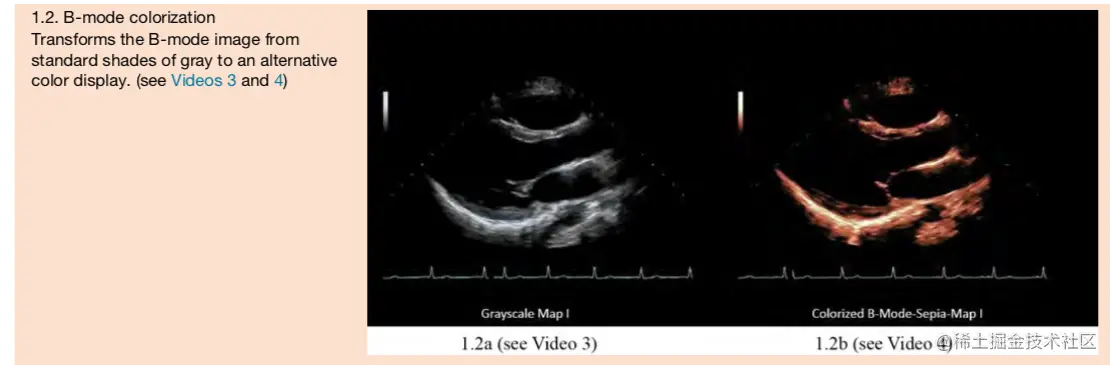

B模式室灰色的,彩色B模式只是从灰色的图转换过去的,包含的信息量室相同的,下图中的信息量室相同的